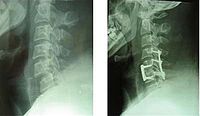

3、手术治疗

手术只能解除对脊髓的压迫和恢复脊椎的稳定性,无法使损伤的脊髓恢复功能。手术的途径和方式视骨折的类型和致压物的部位而定。

手术的指征是:

(1)脊椎骨折,脱位有关节突交锁者:

(2)脊柱骨折复位不满意,或仍有脊柱不稳定因素存在者:

(3)影像性显示有碎骨片凸出至椎管内压迫脊髓者:

(4)截瘫平面不断上升,提示椎管内有活动性出血者。 MRI显示脊髓内有出血者可在脊髓背测正中切开脊髓至中央沟,清除血块与积液,有利于水肿的消退。 手术后的效果术前年年难以预料,一般而言,手术后截瘫指数可望至少提高一级,对于完成性截瘫而言,提高一级并不能解决多少问题,对于不完全性截瘫而言,提高一级移意味着可能改善生活质量。为耍杂诓煌耆越靥闭吒Τ只取U庖辉蚋褂糜诔戮尚怨钦邸?